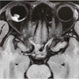

- MRI used to evaluate a child with retinoblastoma. Note the white tumor on the T1 weighted image. There is no evidence of extrascleral or intramural invasion nor PNET.